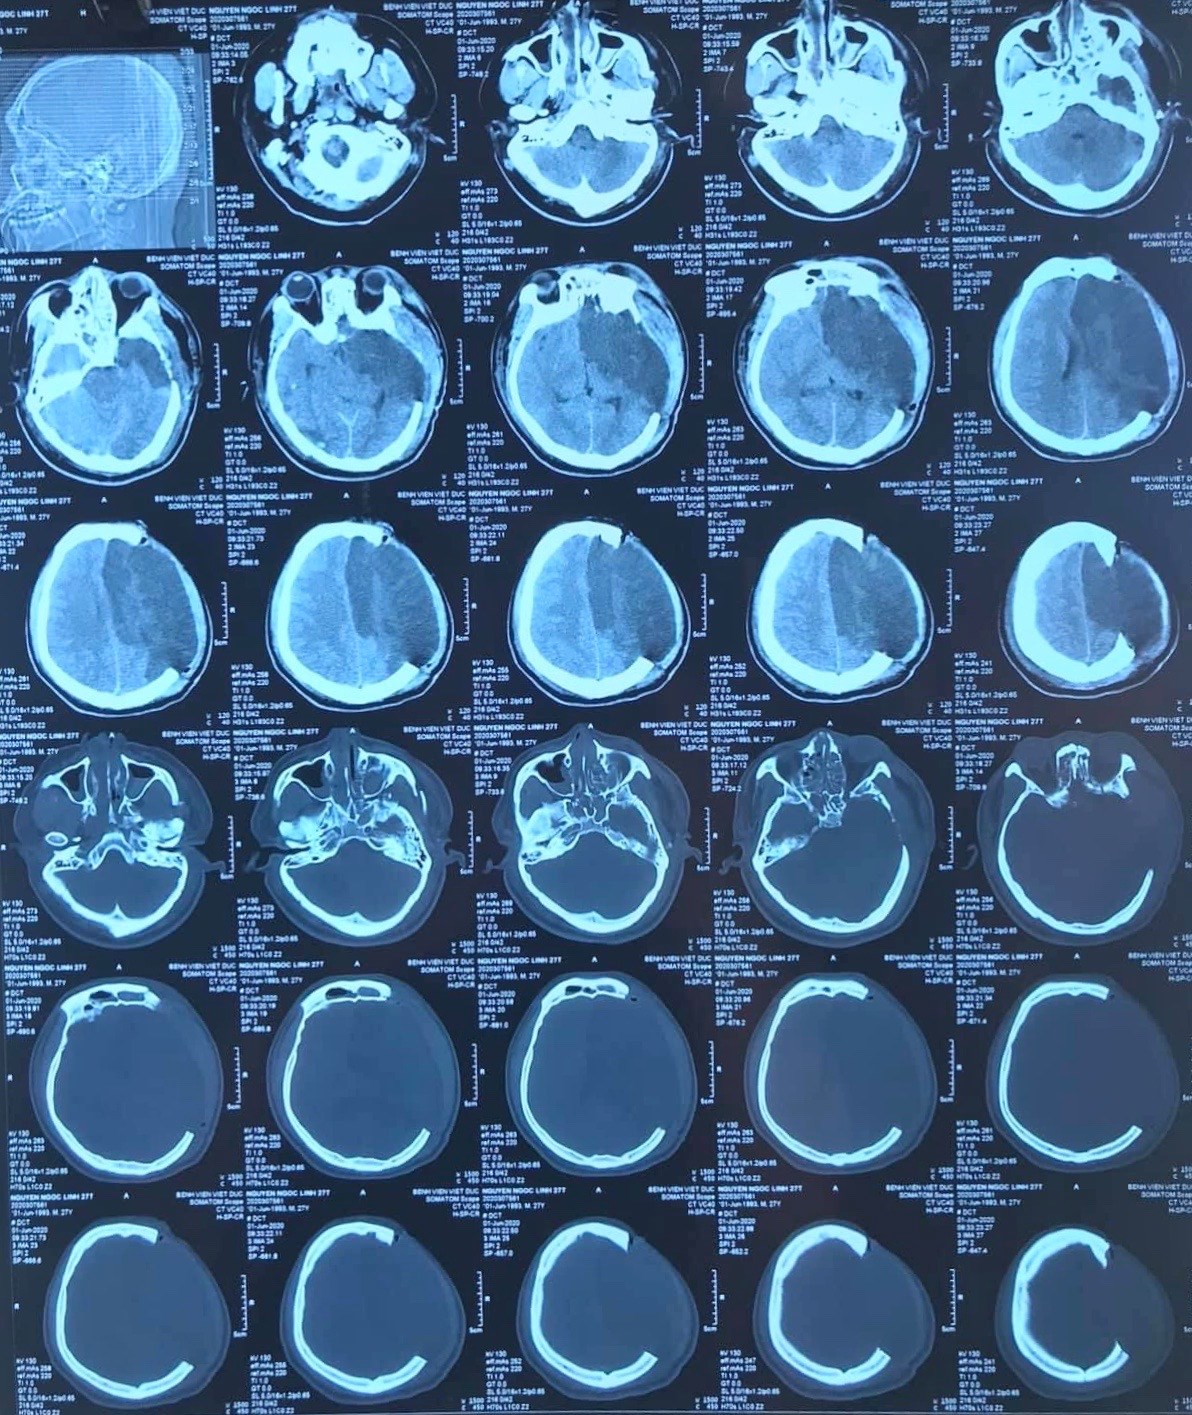

| Kiểm tra sau lấy dị vật. Ảnh: Bệnh viện Hữu nghị Việt Đức |